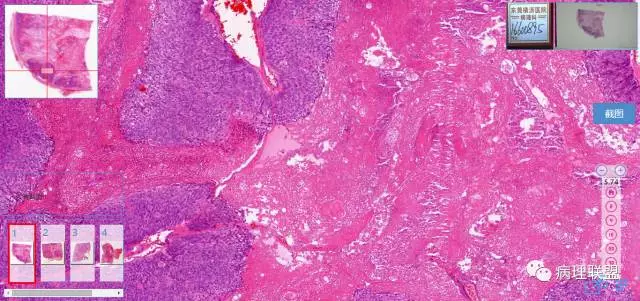

第一例

第一例和第二例病例我把典型图像压下来,是让我们以后注意,典型里找不典型,毛母质瘤主要由两种细胞构成,嗜碱细胞和影细胞构成,主要认识嗜碱细胞。